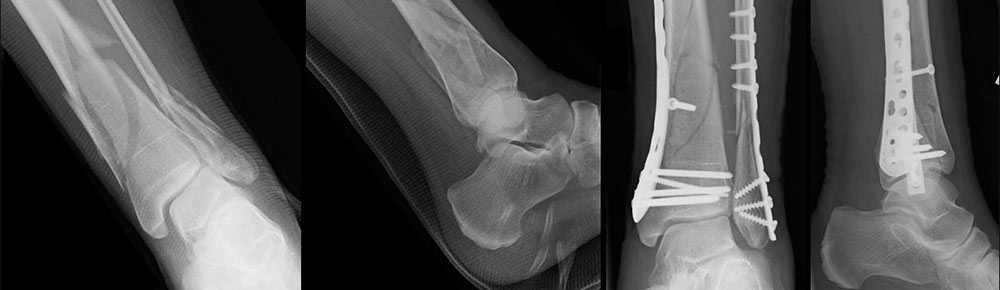

Unfallchirurgie

Wir behandeln das breite Spektrum der unfallchirurgischen Verletzungen, vom einfachen Knochenbruch bis hin zu komplexen Traumata und deren Folgen.